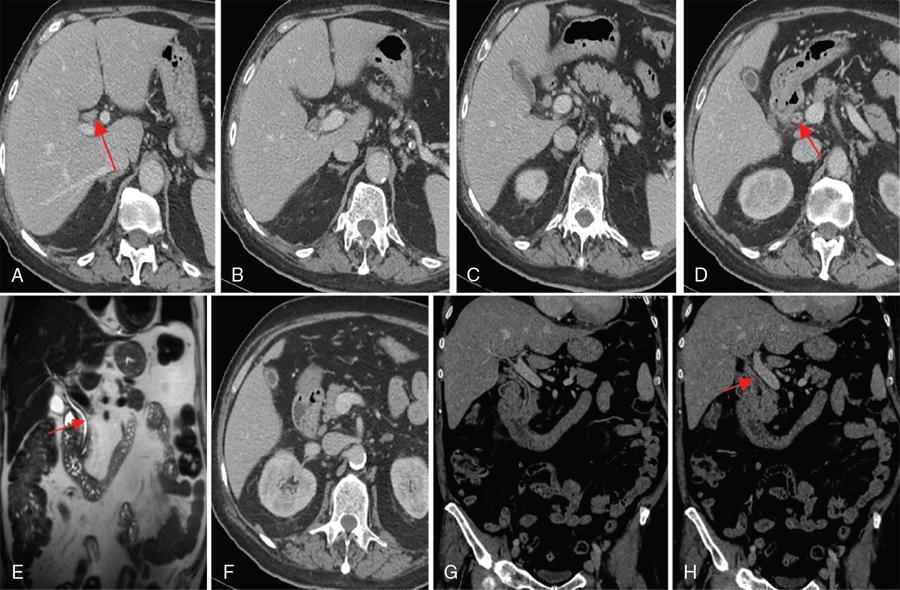

Ritu K. Kashikar, Shrinivas B. Desai, Chandresh Karnavat, Nilesh Doctor The biliary tract is subject to a variety of abnormalities. The spectrum includes benign diseases of autoimmune, infective, ischaemic, infiltrative aetiologies and malignant disorder, which most importantly represents cholangiocarcinoma. Imaging in particular magnetic resonance cholangiopancreatography (MRCP) plays a vital role in diagnosis and follow-up of these disorders. Multidetector computed tomography (MDCT) and magnetic resonance imaging (MRI) are also crucial in preoperative staging of biliary malignancies and making decisions regarding resectability and extent of resection. This chapter focuses on important benign and malignant disorders of the biliary tree and imaging features that aid in differentiation of various entities. A variety of disorders affect the biliary tree. Most biliary disorders manifest as biliary dilatation. The various causes are listed in Table 9.15.1. Imaging plays an important role in identification of aetiology based on pattern of involvement in association with clinical picture. USG is often the first investigation in a patient with jaundice. USG is excellent at showing biliary dilatation. It may be useless in assessing level of obstruction and biliary stones. Changes in liver morphology, development of cirrhosis is accurately done on USG. Early changes in conditions like primary sclerosing cholangitis (PSC), presence of intrahepatic ductal strictures, thickening of common bile duct (CBD) are, however, not confidently seen and need imaging modalities like MRCP and computed tomography (CT). Staging of hilar cancers is also best done on CT or MRI with contrast. Contrast-enhanced CT is extremely accurate in staging hilar cancers. It is a preferred modality to access radial spread of the disease and vascular involvement. Subtle changes of PSC and autoimmune cholangitis may however be missed and MRCP is preferred in these conditions. The protocol for evaluating biliary disease is standard plain scan followed by early, late arterial, portal venous and parenchymal phases similar to that obtained for focal liver lesions. Delayed phase images should be obtained for hilar malignancies, which often show delayed enhancement. MRCP with or without contrast is the modality of choice in diagnosing and characterizing biliary diseases. Owing to its noninvasive nature, it has replaced endoscopic retrograde cholangiopancreatography (ERCP) in the initial evaluation and follow-up of a variety of biliary pathologies. Absence of radiation exposure makes it suitable to obtain follow-ups in patients requiring serial scanning. The ability to diagnose abnormalities of both intra- and extrahepatic biliary tree, level of obstruction, longitudinal and radial spread of neoplastic process make it an ideal modality. MRCP protocol includes T2 weighted single-shot fast spin-echo, T1 weighted in phase and opposed phase gradient echo, diffusion-weighted imaging, T2-weighted fat-suppressed fast spin-echo in axial and coronal. A pre contrast three-dimensional T1-weighted fat-suppressed spoiled gradient-echo image is obtained in addition to 3-D MRCP. Postcontrast protocol includes dynamic three-dimensional T1-weighted fat-suppressed spoiled gradient-echo (in arterial, late arterial and portal venous, parenchymal and delayed phases). Since the advent and widespread use of MRCP, the utility of ERCP in diagnosing biliary pathologies has significantly reduced. ERCP is primarily used when stenting or other procedures need to be performed in the same setting. Although an invasive procedure with postprocedural risk of pancreatitis ERCP allows excellent depiction of biliary changes in conditions like PSC, recurrent pyogenic cholangitis (RPC) and IgG4-related disorders. Endoscopic USG (EUS) is an excellent modality in diagnosing lower bile duct pathologies and also has the added advantage of obtaining a biopsy in the same setting. EUS is less invasive than ERCP and overall safer. PSC is a premalignant cholestatic liver disorder characterized by bile duct strictures secondary to bile duct inflammation and fibrosis. Cirrhosis of liver can develop secondary to this condition and patients are at a high risk for biliary and colonic cancers. PSC is a relatively rare disease, with an incidence of less than 50 per 100,000 patients though it varies in various location. It is diagnosed in young patients aged 30–40 years and is twice as common in men than in women. Similar to other autoimmune diseases, genetic susceptibility is likely to be instrumental in the development of PSC after exposure to a trigger. There is also a strong association between PSC and human leukocyte antigens (HLAs). Environmental factors such as childhood microbial exposure also play an important role in disease pathogenesis. A strong association of PSC with inflammatory bowel disease (IBD) is seen. There is a 100-fold increased risk of developing PSC among siblings. PSC can be asymptomatic but may present with cholestatic symptoms such as jaundice, pruritus, fatigue and right upper quadrant pain, steatorrhoea and episodes of acute bacterial cholangitis. There is marked elevation of alkaline phosphatase (ALP). A twofold to threefold increase in serum alanine and aspartate aminotransferase (AST) can be seen. Elevated bilirubin is usually seen in advanced disease, malignancy or those with choledocholithiasis. Various serum antibodies can also be elevated in PSC. These have been enlisted in Table 9.15.2. On liver biopsy, classic pathologic features of periductal concentric fibrosis or ‘onion skin’, around the affected ducts can be seen. This is however not a pathognomonic finding and is seen in less than 40% of biopsy specimens. Therefore, biopsy is not routinely used as a diagnostic tool for PSC and is reserved primarily for disease staging. MRI with MRCP best depicts the biliary changes in PSC and is the modality of choice. While CT and USG may show biliary dilatation and changes of cirrhosis in advanced cases, they fail to show early changes (Table 9.15.3). USG is an effective modality for the visualization of dilatation and diffuse wall thickening of the extrahepatic bile duct. Other feature seen on USG is bright echogenic portal triad. However, the role of USG in the diagnosis of early PSC is limited owing to suboptimal assessment of the intrahepatic biliary ducts. Features of advanced disease such as heterogeneous coarse echogenicity can be readily detected with USG. The major benefit of performing US is to guide liver biopsy. Also, liver stiffness as assessed by transient elastography correlated well with the degree of liver fibrosis in PSC patients. CT can demonstrate some findings suggestive of sclerosing cholangitis such as focal, discontinuous, often peripheral intrahepatic biliary duct dilatation and thickening with enhancement of the bile ducts owing to inflammation. CT is effective in helping exclude other causes that can result in biliary stasis and dilatation such as hepatic and pancreatic lesions. CT is also excellent in diagnosing tumours, which may sometimes have similar presentation. Concomitant changes of IBD, if present, can be seen. However, CT is limited in assessment of biliary strictures and visualization of disease involving small peripheral bile duct, especially in the early stages of the disease. CT shows changes of cirrhosis in liver and assessing changes of portal hypertension. MRCP is diagnostic imaging modality of choice in the workup of patients with suspected PSC, as recommended by both the AASLD and EASL guidelines. MRCP has high diagnostic sensitivity (86%) and specificity (94%) for the detection of PSC (Table 9.15.3). Multifocal short segmental strictures in the intra- or extrahepatic biliary tree with intervening normal or dilated duct leading to beaded appearance are seen in early disease. The location in strictures is usually at the biliary bifurcation and are disproportionate to upstream dilatation. Advanced cases show pruning of peripheral biliary radicals secondary to advancing fibrosis obliterating the smaller ducts. An obtuse angle between the central and peripheral ducts is suggestive of PSC. Diverticula and webs also can be seen, though not pathognomonic (Table 9.15.4) (Figs. 9.15.1–9.15.3). Strictures of the CBD of less than 1.5 mm and of left, right or common hepatic duct (CHD) of less than 1 mm are defined as dominant stricture. A dominant stricture is associated with worse prognosis in part due to development of cholangiocarcinoma. MRCP plays an important role in raising the suspicion and guiding treatment. A dominant stricture may be confused with hilar cholangiocarcinoma on imaging and it is often impossible to distinguish the two based on imaging alone (Table 9.15.4) (Fig. 9.15.4). Changes in liver morphology are seen in the form of distortion. The classical change described in PSC includes hypertrophy of the caudate lobe and atrophy of the left lateral and right posterior segments of the liver. Hypertrophy of caudate lobe is more frequent in PSC than cirrhosis from other aetiologies. Other parenchymal changes include heterogeneity of liver, periportal cuffing, peripheral inflammation, cirrhosis and features of portal hypertension. Hyperintensity of the liver parenchyma in PSC on nonenhanced T1-weighted images has been reported. Wedge-shaped peripheral atrophic areas of confluent hepatic fibrosis are seen as high T2-weighted signal intensity. Periportal oedema is visualized as high signal intensity in periportal region on T2-weighted. Increased heterogeneous peripheral enhancement of the liver parenchyma can be seen and is likely due to the altered blood supply in those areas in response to parenchymal inflammation (Table 9.15.4) (Figs. 9.15.5 and 9.15.6). MR elastography is the most accurate noninvasive method for the diagnosis and staging of liver fibrosis and could potentially replace liver biopsy. It is predictive of progression to decompensated liver disease. However, lack of wide availability are still major limiting factors. MR elastography is not influenced by obesity or anatomical conditions (e.g. narrow intercostal spaces and ascites) and the sample size of the liver is significantly higher and hence has several advantages over ultrasound elastography (Table 9.15.5). Besides these features, enlarged reactive abdominal lymph nodes, commonly periportal and portocaval lymph nodes, are commonly diagnosed in PSC and should not be misdiagnosed as a lymphoproliferative disorder or metastatic disease. Though ERCP has higher diagnostic accuracy in detecting PSC, its role is limited to intervention required in PSC due to its invasive nature and potential complications. Also it is recommended that MRCP be performed prior to ERCP as a preprocedural MRCP can provide a road map to the endoscopist. Small duct PSC is a variant PSC syndrome with biochemical markers and histologic features suggestive of PSC with normal cholangiography. It is associated with better prognosis. Approximately one-fourth of patients’ progress to classic PSC in an average of 8 years. Bile duct calculi are a common complication of PSC. Pigmented bile duct stones are common owing to biliary stasis. Both intrahepatic and extrahepatic biliary stones can be found. However, the presence of biliary tree stones is not an essential diagnostic feature. Soft calcific foci within dilated bile ducts can be seen on US and CT images. MRI with MRCP is the imaging modality of choice to detect bile duct stones and appear as focal areas of signal-intensity-void filling defects on T2-weighted images. Usually isointense at T1-weighted imaging but frequently are hyperintense. The presence of biliary strictures puts these patients at risk of bacterial cholangitis in PSC patients. The classic Charcot triad of fever, abdominal pain and jaundice can be seen. Early enhancement of the biliary wall due to the biliary duct inflammation is a common finding with peribiliary reactive hepatic parenchymal changes. Cholangitic abscesses may sometimes be seen. PSC patients are at high risk of developing cholangiocarcinoma during the disease course with and a total risk of 10%–15%. Approximately 30% of all cholangiocarcinomas are detected within the first year of establishing a diagnosis of PSC and so it is important to be suspicious even at the time of PSC diagnosis and to survey for early detection. Rapid clinical deterioration, worsening of jaundice, pruritus, weight loss along with elevation in serum bilirubin and ALP should raise suspicion of PSC. It may be difficult to distinguish benign from malignant strictures. Progressive bile duct wall thickening, irregularity, enhancement, new onset biliary dilatation, dominant stricture or development of focal strictures with dilatation and ipsilateral atrophy are indeterminate features that may raise possibility if occult cholangiocarcinomas. Perivascular thickening, vascular involvement or occlusion are features favouring malignancy. Definite diagnosis is however often not possible on imaging alone and a brush biopsy should be taken in patients with new onset clinical symptoms, elevated tumour makers or above-mentioned indeterminate imaging features (Table 9.15.7). The most common subtype of cholangiocarcinoma in PSC patients is periductal type, characterized by long segment irregular wall thickening along the bile duct with no identifiable mass. The lesion is hypointense on T1W1 images and hyperintense on T2W1 images showing progressive enhancement on contrast study. The tumour could be at the bifurcation and can cause abrupt cut-off, commonly presenting as Klatskin tumour (Fig. 9.15.7). Combined UC and PSC is associated with a higher risk for colorectal carcinoma than UC alone. PSC is considered as an independent risk factor for development of colorectal carcinoma in patients with UC. Malignancy tends to involve the right colon or more proximal parts of the colon. Clinical presentation and history in patients with ascending cholangitis differ from those with PSC. Fever, pain and jaundice dominate the presentation in patients with ascending cholangitis while patients with PSC may be asymptomatic. The typical findings of PSC including biliary duct stenosis, beading or pruning are not typical findings in the newly diagnosed cases of acute ascending cholangitis. Wedge-shaped peripheral and/or intrahepatic peribiliary foci of increased T2 signal around the dilated radicals with arterial and/or delayed parenchymal enhancement has been described in ascending cholangitis. Patients with RPC present with recurrent episodes of abdominal pain, fever, jaundice and chills. These features differ from those in patients with PSC. Hepatolithiasis with pigmented stones in the biliary tree and upstream and downstream duct dilatation are typical imaging features in RPC (Table 9.15.8). Ischaemic cholangiopathy is a form of biliary injury resulting from decreased arterial supply. History of liver transplantation is the key in diagnosing ischaemic cholangiopathy. Biliary strictures in AIDS cholangiopathy are indistinguishable from PSC. However, the combination of papillary stenosis and intrahepatic ductal strictures appears relatively unique to AIDS cholangiopathy; this combination is not found in PSC. Clinical history may help to distinguish one from the other. Effective medical therapy for PSC is lacking. Oral ursodiol (ursodeoxycholic acid) is one of the main treatment options of cholestatic diseases though does not prevent disease progression. Azathioprine and steroids are recommended for use in patients with AIH as well as those with AIH–PSC overlap syndrome. Vedolizumab is a gut-specific monoclonal antibody that has been tried but the clinical utility in PSC–IBD patients remains under investigation. Dilatation of biliary strictures, stenting, lithotripsy and stone extraction can be done with the aid of ERCP and percutaneous transhepatic cholangiography (PTC). The only definitive cure of PSC is, however, liver transplantation. Treatment of complications like choledocholithiasis stone removal can be accomplished by using standard endoscopic techniques with or without sphincterotomy, with balloon or basket extraction for extrahepatic biliary stones. For bacterial cholangitis, immediate administration of broad-spectrum antibiotic therapy is recommended and in abscess formation percutaneous drainage with intravenous antibiotic therapy shows favourable outcome compared with surgical drainage. Incidence is 20%–25%. Diagnosis of recurrent PSC requires careful evaluation, as there are other causes of biliary changes after liver transplant with similar features. Nonanastomotic biliary strictures imply the diagnosis of recurrent PSC only if they occur more than 90 days after transplant. Characteristic multifocal strictures and segmental dilatations of biliary ducts are suggestive findings. MRCP is the initial modality. RPC is characterized by a triad of recurrent biliary sepsis, inflammatory biliary strictures and intrahepatic stones. Fifty per cent of patients may have acute pancreatitis. Oriental cholangiohepatitis, primary hepatolithiasis, Hong Kong disease and oriental infestational cholangitis. Prevalence in the third and fourth decades of life with equal frequency among men and women peak. Southeast Asia predominantly in rural population and in lower socioeconomic groups. Gut-derived organisms lead to sepsis, which initiates a cascade of events, which leads to a chronic, progressive and recurrent inflammatory process in cholangioles. Associations with Clonorchis sinensis, Opisthorchis species, Fasciola hepatica and Ascaris lumbricoides infestations have been suggested. Common organisms cultured from bile include Escherichia coli, Klebsiella, Pseudomonas and Proteus species and anaerobes. Structural biliary abnormalities may develop before stones are demonstrable. Strictures may be seen at cholangiography without stones and vice versa. Entrapped stones cause stasis, sepsis, scarring and stricturing with the increasing lithogenicity (Table 9.15.9). Typically present with abdominal pain, fever and jaundice (the Charcot triad) and commonly provide history of repeated episodes. Routine investigations may demonstrate leukocytosis, deranged liver enzymes with obstructive pattern. Elevated cholestatic markers (bilirubin, ALP and gamma GT) and deranged LFTs can be seen. Serum inflammatory markers can be elevated. Additional tests aiding in differential diagnosis include autoantibodies, ANCA, CA19-9 and serologic tests for Echinococcus. Histology is usually not required. It shows fibrous mural thickening of bile ducts and periductal tissue, as well as acute and chronic inflammatory changes. The imaging features include changes in bile ducts, development of calculi and changes in the parenchyma. The disease affects intrahepatic ducts more than the CHD and CBD. Disproportional dilatation of central intrahepatic ducts and extrahepatic bile ducts is seen with nondilated or minimally dilated peripheral ducts, leading to abrupt tapering of bile ducts. All segments of biliary tree may be involved, but the lateral segment of the left lobe is most often and extensively involved most likely because left hepatic ducts come off at a more acute angle compared with the right hepatic ducts, thus predisposing to stasis and stricture formation (Table 9.15.10). Hepatolithiasis is common in patients with RPC. Stones are composed mainly of bile pigments with variable calcification. There may be single or multiple stones scattered in the intra- or extrahepatic ducts or both. The dilatation of the extrahepatic duct is generally not related to the location of the stone. Ducts both proximal and distal to the stone are dilated. Parenchymal atrophy most commonly involves the left lateral and right posterior segments while hypertrophy of the caudate and right lobe is seen. USG shows dilatation of the central intrahepatic and extrahepatic ducts, with relative sparing of the peripheral biliary tree. Hepatolithiasis can be seen in 90% of cases. The echogenicity and acoustic shadowing of calculi may vary depending on extent of calcification. There is often associated periportal echogenicity. Ultrasound may be useful in performing image-guided percutaneous drainage of abscesses or biopsy of suspicious lesions. Limitations include inability to detect subtle intrahepatic ductal dilatation and heavy stone burden obscuring evaluation of underlying hepatic parenchyma. Contrast-enhanced CT is increasingly being used as first line of imaging. It allows for detection of characteristic disproportionate dilatation of the extrahepatic and central intrahepatic ducts. Contrast-enhanced CT also allows for detection of bile duct wall enhancement, suggestive of acute cholangitis. Ninety per cent stones are hyperdense to liver parenchyma on nonenhanced scan. Extent of calcification in calculi may vary. Parenchymal atrophy affects left lateral segment most frequently, followed by right posterior segments. Eventually, changes of cirrhosis can be seen. Heterogeneous appearance of liver parenchyma with segmental steatosis and altered enhancement can be seen particularly during acute attack. Pneumobilia is not infrequent and can usually be attributed to recent procedures or surgeries like bilioenteric anastomosis. It may, however, be seen in patients without history of prior interventions due to recent passage of stone through the ampulla or less commonly cholangitis related to gas forming organisms (Fig. 9.15.8). Subtle intrahepatic ductal strictures and noncalcified stones may be missed on CT. MRCP allows visualization of both intra- and extraductal disease and can reveal complete extent, severity and complications of the disease. Even noncalcified calculi which may be missed on CT or sonography, are seen as intraductal filling defects on heavily T2-weighted images and may appear hyperintense to the liver on T1-weighted images. MRI demonstrates central and extrahepatic duct dilatation with decreased arborization and abrupt tapering of peripheral ducts. MRI particularly MRCP sequences accurately depicts stenotic segments and delineates the entire biliary tree, including the proximal part of the stricture, without risk of aggravating biliary sepsis. Even short segment duct strictures <1 cm are easily seen on MRCP (Figs. 9.15.8 and 9.15.9). Parenchymal abnormalities like hepatic atrophy, whether diffuse or segmental, and altered signal can be accurately diagnosed. Mass lesions and hepatic abscesses, if present, are also well delineated. The characteristic finding of disproportionate dilatation of the ducts, with multiple intraductal calculi are well demonstrated. There may also be intrahepatic strictures, with abrupt tapering of the peripheral ducts as well as decreased arborization of the biliary tree (arrowhead appearance). It allows for better spatial resolution, thus permitting better evaluation of the smaller peripheral ducts. The main limitation of ERCP is its invasive nature, with complications such as ERCP-associated pancreatitis. Heterogeneous parenchymal enhancement, wall thickening and periductal enhancement are seen in acute cholangitis. Abscess formation is encountered in up to 20% of RPC patients who undergo cross-sectional imaging. The abscesses can occur in both the affected and unaffected portions of the liver but most commonly seen in the right lobe. Sonography guided aspiration can be done when diagnosis is doubtful. Intrahepatic bile lakes are not infrequent and may or may not communicate with the biliary tree. On USG bilomas appear anechoic and are usually hypodense on CT with or without calculi. Leakage of bile from a severely dilated obstructed duct may lead to formation of extrahepatic biloma. Cholangiocarcinoma is the most feared complication and may be seen in up to 5% of patients. Segments with high stone burden or those with atrophy are more prone to developing cholangiocarcinoma. Clinical and laboratory indicators for development of cholangiocarcinoma in patients with PSC include increase in jaundice without associated cholangitis, sudden weight loss, significant elevation of ALP and rising tumour markers. Peripheral cholangiocarcinoma manifests as expansion of the affected segment. Hypoattenuating mass with showing peripheral enhancement causing narrowing of the portal vein may raise suspicion of malignancy. Portal vein thrombosis has also been reported but is rare. Recurrent biliary sepsis may lead to periductal inflammation and portal thrombophlebitis. Portal thrombosis can lead to lobar atrophy with compensatory hypertrophy of the uninvolved lobe. Higher incidence of hepatocellular carcinoma (HCC) is reported in patients with RPC due to development of cirrhosis in severe cases. Management should comprise antibiotic treatment, clearance of stones, maintenance of biliary drainage and long-term follow-ups. ERCP allows for therapeutic procedures such as stone removal and stenting of strictures. Destroyed liver segments, those with multiple abscesses and patients with secondary cholangiocarcinoma are candidates or surgery. Stone extraction can also be done surgically with the aid of basket, forceps, balloon catheter or flexible choledochoscope. Transduodenal sphincteroplasty and hepaticojejunostomy are commonly performed drainage procedures. Indications for transplantation include extensive bilobar hepatolithiasis, cirrhosis and liver failure. IgG4 cholangiopathy is a cholangitis characterized by elevated serum IgG4 and infiltration of the bile duct wall with IgG4 positive plasma cells leading to storiform fibrosis and obliterative phlebitis with resultant bile duct wall thickening. This condition shows good response to steroids. Frequent association with IgG4-related autoimmune pancreatitis is seen. IgG4 sclerosing cholangitis (IgG4-SC) has a threefold to fivefold higher prevalence in men than women. It usually presents in the fifth and sixth decades of life. Incidence of this disease is approximated to be around 0.28–1.08/100,000. Autoimmunity has been considered as the most probable pathogenesis of IgG4-related disease (IgG4-RD). Several HLA association have identified as determinants of disease susceptibility. The major histologic features associated with IgG4-RD have been well described and include the steps. Chronic or recurrent cholangitis is the most common presentation and seen in up to 75% cases. Other symptoms seen are fever, pruritus, pain and weight loss. Biliary involvement may be detected incidentally in patients being scanned for symptoms related to involvement of other organs such as pancreas. One-quarter of patients with IgG4-SC may be asymptomatic. Serum liver tests show a cholestatic pattern with often marked elevation of ALP and γ-GT and only mildly increased ALT and AST. Serum bilirubin may be increased. Tumour marker CA 19-9 is not able to distinguish pancreatobiliary malignancies from IgG4-SC since levels of >1000 IU/mL (ULN = 37 IU/mL) may be observed in IgG4-SC. IgG4 levels are elevated (>140 mg/dL) in up to 75%–80% of affected patients. A cut-off level of 207 mg/dL might be useful for completely distinguishing IgG4-SC from cholangiocarcinoma. Elevated bile fluid IgG4 has a high sensitivity and specificity of 100% at a cut-off level of 113 mg/dL and seen only in cases of IgG4-RD, neither PSC nor cholangiocarcinoma. Approximately 40% of patients have peripheral blood eosinophilia, often accompanied by asthma and atopy. Patients may show hypergammaglobulinemia, elevated serum IgE. Several diagnostic criteria have been developed to aid in the diagnosis of IgG4-SC. The most widely used is the HISORt (Histology, Imaging, Serology, other Organ involvement and Response to therapy) criteria of the Mayo Clinic. This tool was initially used to diagnose AIP but can be adapted to diagnose IgG4-SC by Ghazele et al. (Tables 9.15.13 and 9.15.14). It is often the initial investigation and may be normal early in the course of the disease. Circumferential thickening of the bile ducts with biliary dilatation is seen later in the disease. US also helps in the identification of associated findings affecting other organs. However, US has low sensitivity in detecting the disease and is suboptimal for assessing the extent of the disease. Contrast-enhanced CT though not the investigation of choice shows bile duct wall thickening with proximal mild dilatation. The intrapancreatic bile duct segment is more commonly involved. The most important finding is circumferential symmetric wall thickening of the bile ducts, frequently involving the extrahepatic segments, with smooth outer and inner margins. In addition, the thickened segment shows progressive homogeneous contrast enhancement, further increasing in the delayed phase. As opposed to malignancies, wall thickening or stricturing of bile ducts in IgG4-RD is not associated with proportionate proximal biliary dilatation (Figs. 9.15.10 and 9.15.11). In addition to the above findings, imaging findings of IgG4 disease affecting other organs, that is, gallbladder wall thickening, changes of autoimmune pancreatitis, retroperitoneal fibrosis and kidney findings can be seen. MRI is the investigation of choice. MRI findings are similar to CT findings and include circular and symmetric long segmental thickening of the bile duct wall with smooth outer and inner margins. Bile duct wall thickening can be seen in nonstenotic areas as well The other findings are the visibility of patent bile duct in the strictures, disproportionate proximal dilatation, hyperenhancement during the late arterial phase, homogeneous hyperenhancement during the delayed phase, concurrent gallbladder wall thickening and no vascular invasion (Table 9.15.15).